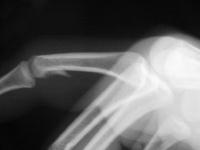

Clinical Example: Unicondylar proximal phalanx head fracture with micro screws

Unicondylar fractures of the phalangeal head are common, frequently unstable and unacceptably displaced. Although some may be treated successfully with percutaneous reduction and fixation, many require open reduction. In these cases, the screws were put right through the collateral ligament and sunk into the cortex. I think the simplest way to do this is to reduce and stabilize with two K wires, then remove the wires and replace with screws, one at a time, so reduction is maintained throughout. 1mm=39/1000" Kwire, so doing the math, here is how you choose the right sized Kwire to use as both drill and provisional fixation:

With two screws, bicortical fixation is not needed. The video below illustrates the steps involved, which are the same with either open or percutaneous fixation.